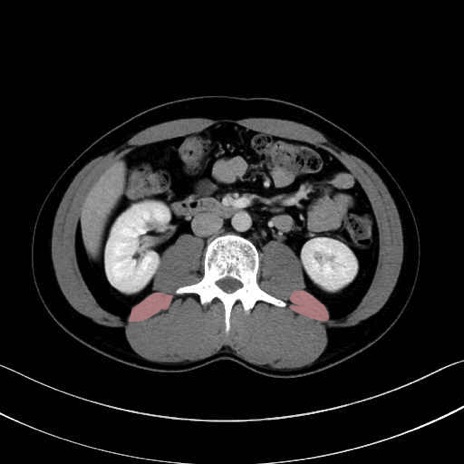

腰方形筋 (Quadratus lumborum)

2. 腸腰筋群と骨盤底筋

大腰筋 (Psoas major)

腸骨筋 (Iliacus)